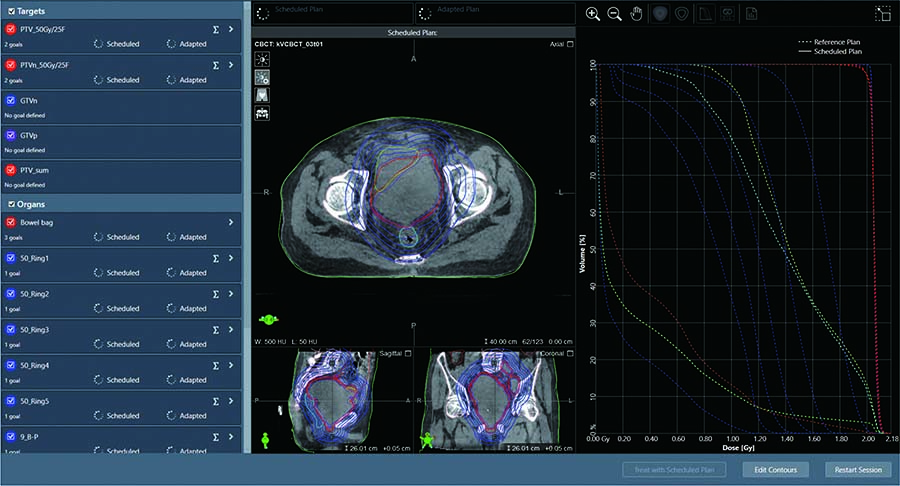

Al-driven Adaptive Radiotherapy Platform

√Al-guided Workflow

The Ethos system imported by our hospital is the world’s first online adaptive radiotherapy system based on artificial intelligence technology. It builds upon conventional linear accelerators by incorporating cutting-edge technologies such as artificial intelligence, multimodal high-definition imaging, efficient imaging scanning, and online quality control systems, enabling efficient online adaptive radiotherapy.

The online adaptive radiotherapy of Ethos obtains the patient’s current position image before treatment every day, uses artificial intelligence to adjust the target area and modify the plan in real time, so that every time the patient is treated, the radiation can be accurately projected to the tumor area, achieving accurate individualized radiotherapy every time. It has obvious advantages, especially in prostate cancer, bladder cancer, cervical cancer, endometrioma, rectal cancer and other tumors in parts that change greatly with the filling degree of the intestine and bladder.